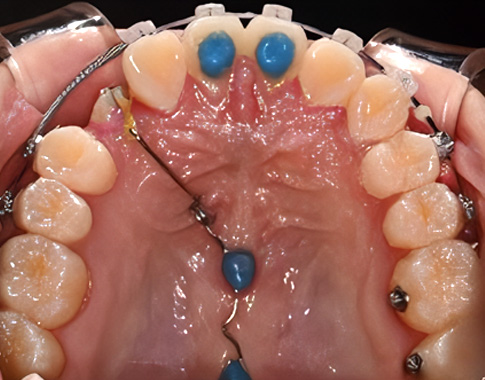

Impacted Tooth

숨어있는 치아교정,

매복치

매복치아나 늦게 나오는 치아 때문에 걱정되시나요?

교정치료를 통해 숨어있는 치아가 자연스럽게 나올 수 있도록 도와드립니다.

아이의 건강한 치아 배열을 위해 적절한 시기에 시작하세요.